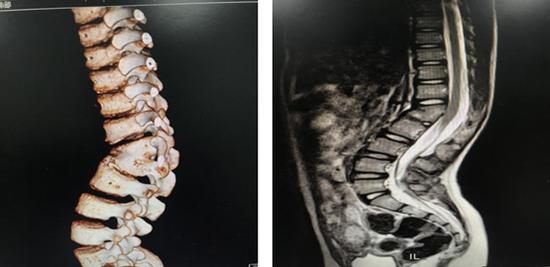

图2和图3是一个患有先天性脊柱侧弯的儿童,他的侧凸在手术后持续恶化.

> 正文 此例接受手术的患儿腰背部后凸畸形6年,诊断为先天性脊柱胸